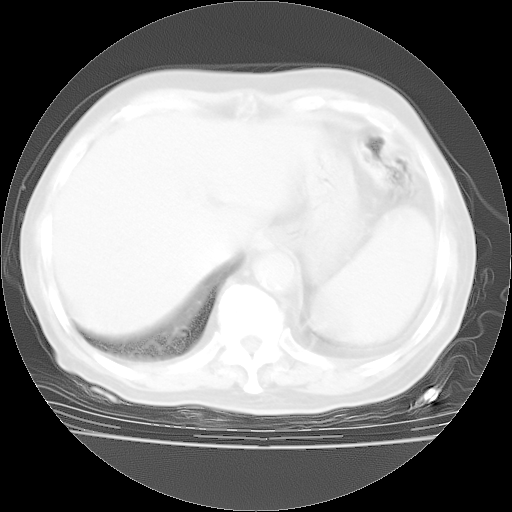

4月28日肺部CT——再次出现类似去年5月9日——透光度降低,“间质性”改变。

4月28日肺部CT——再次出现类似去年5月9日——磨玻璃样、间有“粟粒样”改变。

4月28日肺部CT